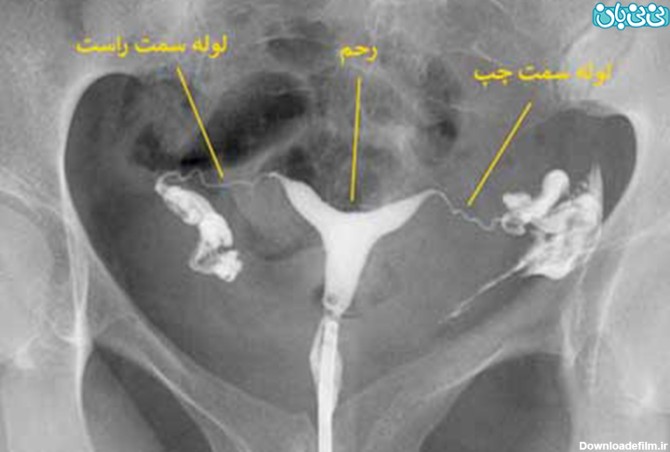

عکس رنگی رحم یا هیستروسالپنگوگرافی روشی است که به منظور بررسی داخل رحم و لوله های رحمی انجام می گیرد و انجام آن در ارزیابی ناباروری بسیار مهم است.

"هیستروسالپنگوگرافی" یا "عکس رنگی رحم" یک روش تصویر برداری است که به پزشک کمک میکند تا با استفاده از اشعه ایکس داخل رحم و لوله های فالوپ را مشاهده کند. این

عکس رنگی رحم یا هیستروسالپینگوگرافی به معنای استفاده از اشعه ایکس برای مشاهده رحم و لولههای فالوپ است.